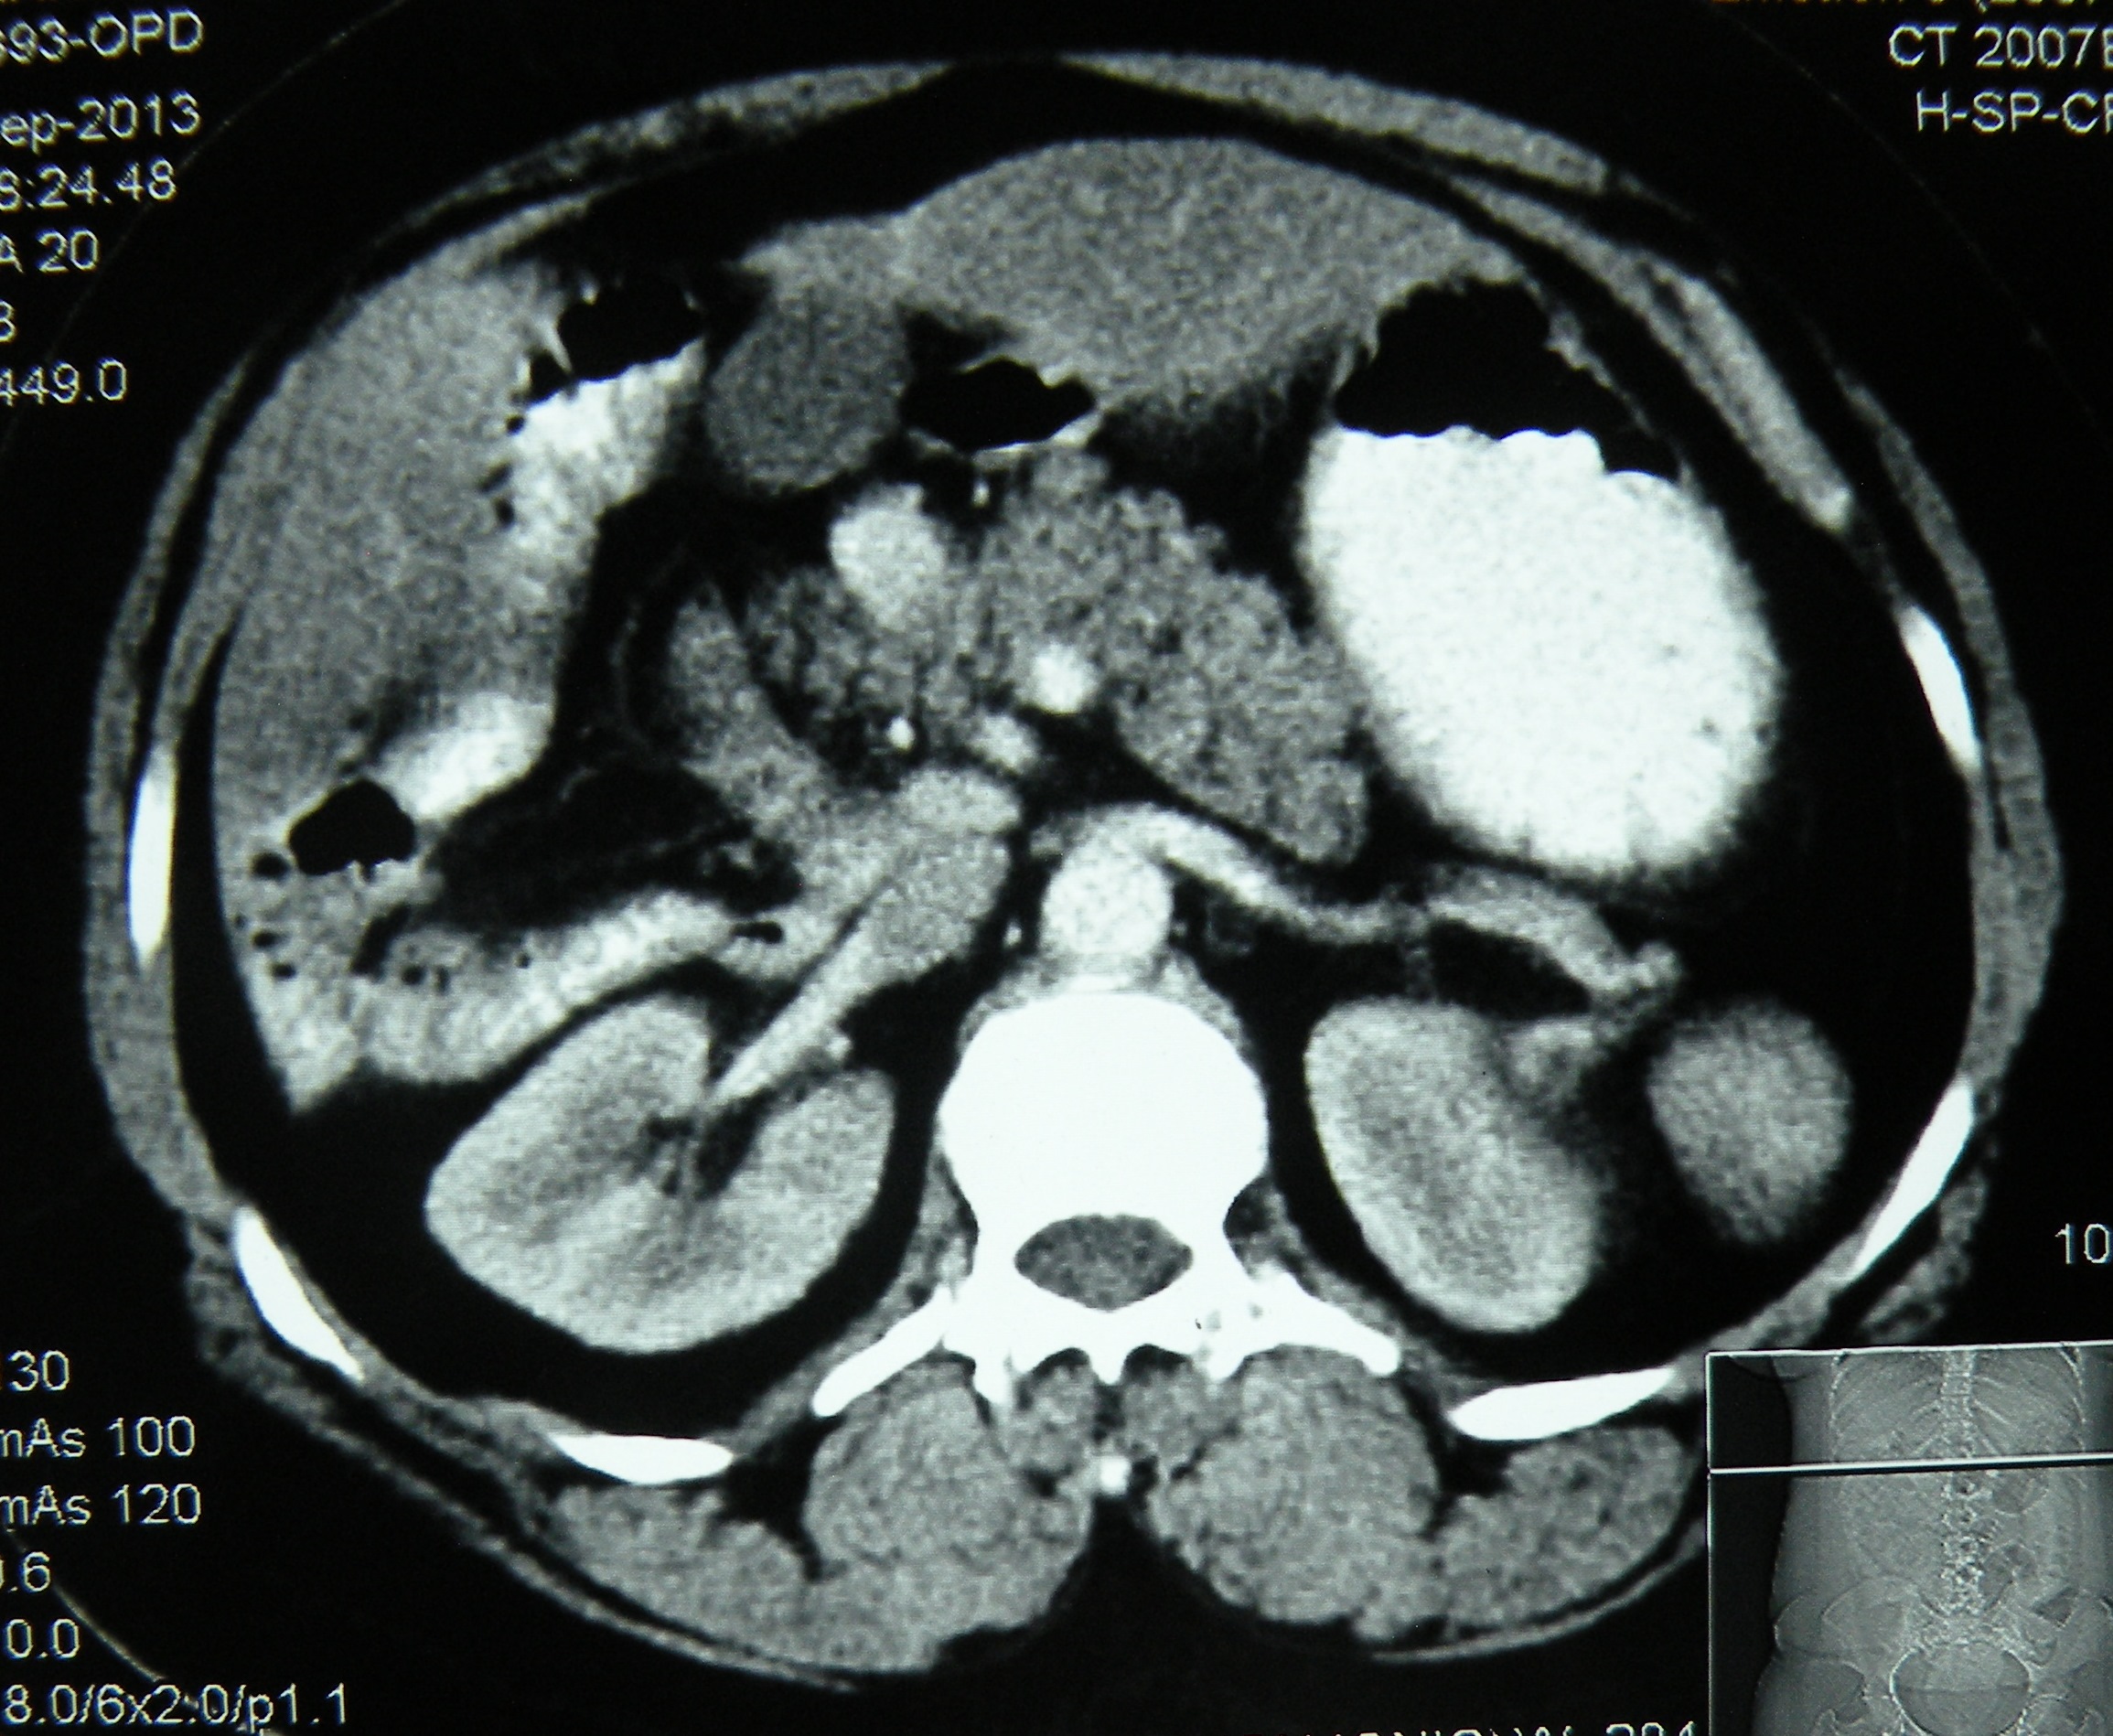

Situs ambiguous(heterotaxia) with gall stones, an ileal carcinoid? and bad encounters with chronic liver disease

An interesting case of situs ambiguous (heterotaxic syndrome) presented with history of failed open attempt at civil hospital, Nabha to remove her gallbladder which could not be found by the surgeon. Imaging (US, CT, MRI) here showed a central liver, with gallbladder placed in the centre between the two lobes, polysplenia, truncated pancreas and dextrocardia. At surgery, the gall bladder was found just to the left of the falciform ligament. A difficult lap chole (due to dense adhesions with falciform ligament and omentum) was done, with the main operating port in the LUQ of the abdomen.

| CASE REPORT Year : 2014 | Volume : 4 | Issue : 3 | Page : 180–182 Laparoscopic cholecystectomy in situs ambiguous Anoop Varma1, Abhinav Mahajan1, Mohinder Singh1, Gunjeet S Sandhu1, Navkiran Kaur2, |